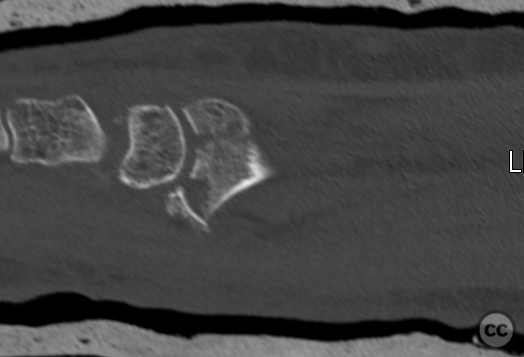

Clinical and radiological findings:  A 72-year-old female sustained a multifragmentary, dorsally displaced distal radius fracture after a fall down stairs. Initial reduction revealed a 180-degree flipped fragment of the volar ulnar articular margin, unreducible by closed means. There was no mention of associated neurovascular compromise or open injury. Radiographs and intraoperative fluoroscopy confirmed the presence of a multifragmentary intra-articular fracture (AO/OTA 23-C3), with a flipped volar ulnar fragment and radial styloid impaction. The distal radioulnar joint alignment was restored postoperatively.

Anatomical surgical approach:  A longitudinal incision was made over the flexor carpi radialis (FCR), zigzagging over the wrist crease. Subcutaneous dissection and incision of the FCR tendon sheath were performed, followed by transection of musculus pronator quadratus fibers along the radial border of the distal FCR. The FCR tendon was retracted ulnarly, and the antebrachial fascia incised. Musculus flexor pollicis longus was identified and retracted ulnarly. The pronator quadratus was incised along its radial border and the watershed line, then elevated subperiosteally to expose the distal radius. Extended distal release of the FCR allowed wide exposure of the ulnar aspect of the lunate facet and volar lip. The flipped volar ulnar fragment was de-rotated and provisionally fixed with a Kirschner wire. Ligamentotaxis for radial styloid reduction was achieved using Kirschner wires in the scaphoid and distal radius, with a wire spreader applied for distraction. Provisional fixation was achieved with multiple Kirschner wires. A mini-fragment T-plate, cut and shaped as a hook plate, was applied to the volar ulnar lip fragment, fixed with bicortical screws, and used to engage dorsal fragments. The radial styloid was addressed with a contoured T-plate, similarly fixed with bicortical locking screws. Final multiplanar fluoroscopy confirmed anatomical reduction and hardware placement.

The flipped volar ulnar articular margin fragment was irreducible by closed means due to capsular attachment and required direct open de-rotation and fixation. The impaction and proximal displacement of the radial styloid fragments were challenging due to persistent traction from musculus brachioradialis and scaphoid pressure; ligamentotaxis using Kirschner wire spreader over the scaphoid facilitated reduction. Fragment-specific fixation was necessary: a custom-shaped hook plate for the volar ulnar lip fragment provided stable fixation and prevented dorsal instability, while a separate T-plate addressed the radial styloid. Bicortical locking screws were used to secure both plates, with some screws engaging dorsal fragments from the volar side. Careful adaptation of pronator quadratus over hardware minimized risk of musculus flexor pollicis longus irritation. Additional suture stabilization of radiocarpal ligaments to pronator quadratus provided secondary ligamnetal support.